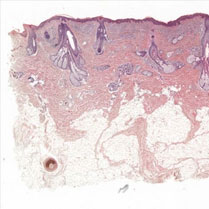

Epithelial cells and the sheets they produce, including our skin, are incredibly strong thanks

to their internal keratin filament cytoskeleton networks